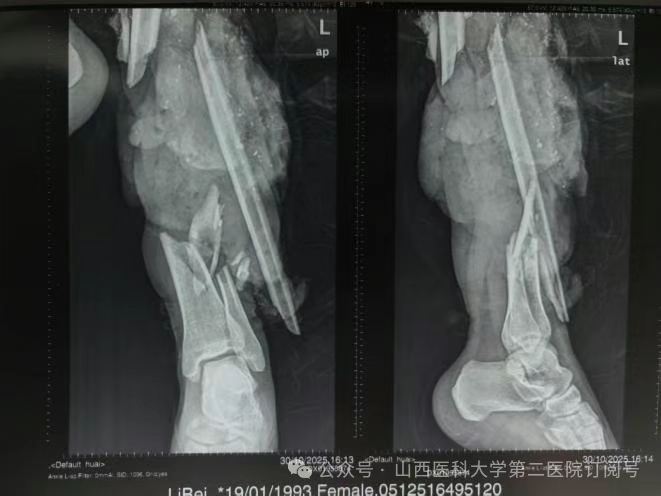

患者不慎在十字路口被右拐挂车剐蹭摔倒,致使左小腿中段被半挂车轮大力碾压,左胫腓骨完全性、毁灭性缺损,软组织条件极差,左下肢仅剩不到四分之一的皮肤与身体相连,其余肌肉骨骼难觅其踪,左膝以下动脉已被闭塞血供消失。不幸中的转机是患者左踝以下保存完好,踝关节面未见明显损伤,因严重外伤导致左小腿胫腓骨完全性、毁灭性缺损,软组织条件极差。按照常规诊疗思路,如此严重的损伤,截肢或许是“最稳妥”的选择。但截肢意味着患者将永久失去左膝以下肢体,未来的假肢适配、步态训练、心理创伤都是漫长而艰辛的过程。经过张桦栋医师团队严谨的术前讨论和精密的设计,一个大胆而富有创造性的手术方案被最终确定:左下肢旋转成形术。

骨科总住院医师张桦栋医师介绍:“这个手术的理念堪称重塑。其核心原理是将受损严重的左小腿部分及左膝切除,保留功能完好的足部,并将其旋转180度后,与大腿股骨进行固定融合。这样一来,原本的踝关节就扮演起了膝关节的角色。形象地说,这就像进行了一次精密的“人体拼装”:将脚踝调转方向,与大腿连接。术后,通过专业的康复训练,患者可以利用这个“新的膝关节”(即原来的踝关节)进行屈伸活动,从而驱动假肢,实现更自然、更有力的行走。这远比传统大腿截肢后佩戴的假肢功能更优,能量消耗更少,步态也更接近正常人。